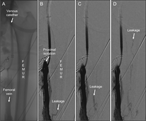

Inferior gluteal artery surgical access for embolization of large internal iliac artery aneurysm in a hostile abdomen

Konstantinos Tigkiropoulos and others

Journal of Surgical Case Reports, Volume 2019, Issue 4, April 2019, rjz098, https://doi.org/10.1093/jscr/rjz098